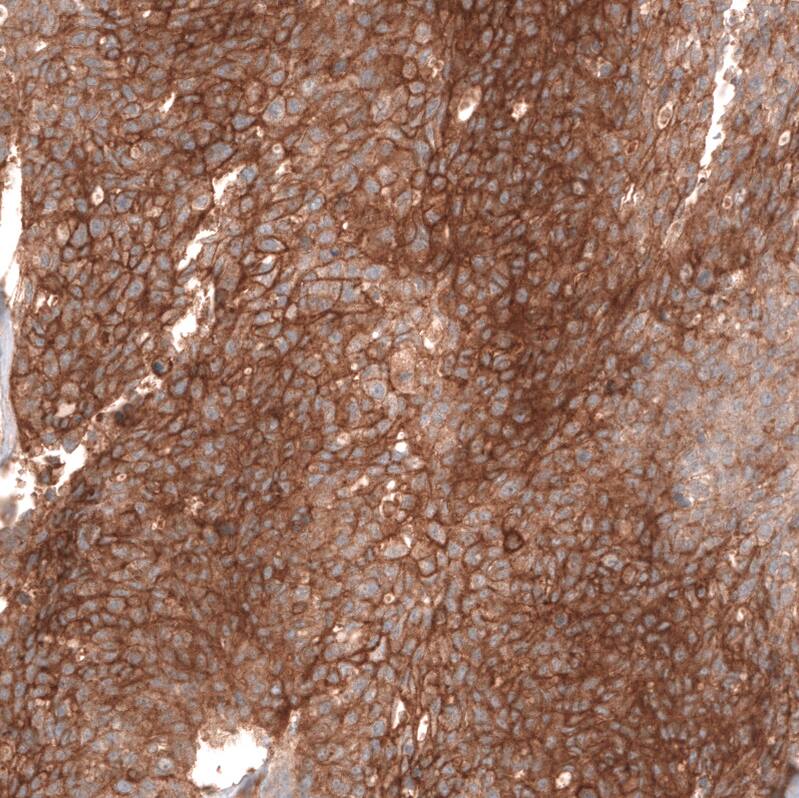

Immunohistochemistry-Paraffin: FXYD5/Dysadherin Antibody (CL14037) [NBP3-24585]

Staining of human breast cancer shows strong membranous positivity in tumor cells.